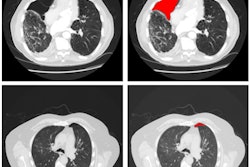

In the other ECR 2018 presentation, researchers from Optellum shared how their deep-learning algorithm could help avoid unnecessary workup in patients with benign lung nodules.

The Optellum group initially curated the entire NLST dataset, focusing on solid and semisolid nodules at least 6 mm in diameter. All malignant nodules and the earliest benign nodules were included for each patient, resulting in a total of 5,622 nodules from 6,325 patients. Among the 5,622 nodules, 4,842 were benign and 780 were malignant.

Next, the researchers trained a convolutional neural network (CNN) using fourfold cross-validation. In testing, they found that 19% of benign nodules could be effectively ruled out by the algorithm, while maintaining a 0% false-negative rate.

"This implies that we could potentially avoid unnecessary workup or follow-up of nodules, reducing patient stress and unnecessary procedures," said presenter Carlos Arteta, PhD.